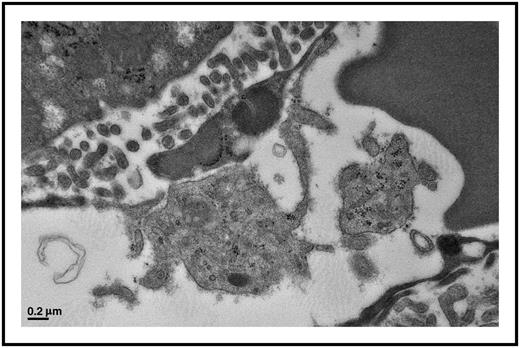

Platelets actively interact with liver endothelial cells in a Plasmodium berghei infection model. This platelet has formed a distinct contact interaction with the endothelial cell. These interactions occur in many tissue beds and with circulating immune cells contributing to the inflammatory pathogenesis of cerebral malaria. Electron microscopy image; scale bar, 0.2 μm.

The work of numerous laboratories has shown that platelets are key mediators of both immune responses and immune development. Platelets contain a large and diverse array of granule-stored chemokines and cytokines, and when stimulated, platelets also de novo produce inflammatory molecules that promote leukocyte activation and trafficking, as well as vascular inflammation. Although small in size (∼2 µm in diameter), platelets have major immune effects due to their circulating numbers (∼200 000/µL in humans) and the numerous inflammatory molecules they contain. Malaria-infected red blood cells (RBCs) can activate platelets that increase cerebral vasculature endothelial inflammation, leukocyte recruitment, and loss of the blood-brain barrier. Immune and endothelial cell responses to infection also induce vascular inflammation, more local platelet activation, and platelet interactions with an intact and inflamed endothelial cell layer, further driving platelet adhesion, activation, and an amplification of vascular inflammation. Direct antibacterial properties have been described for platelets, including bacteria engulfment and clearance and the release of microbicidal proteins from platelets,2 leading to speculation that, similar to other immune cells, platelet immune responses may be protective and beneficial by directly clearing and killing pathogens.